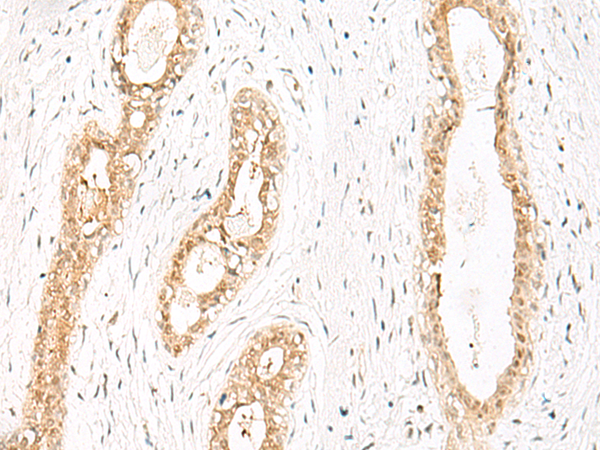

ELISA, IHC |

IHC positive control: |

Human thyroid cancer and Human cervical cancer |

IHC Recommend dilution: |

30-150 |